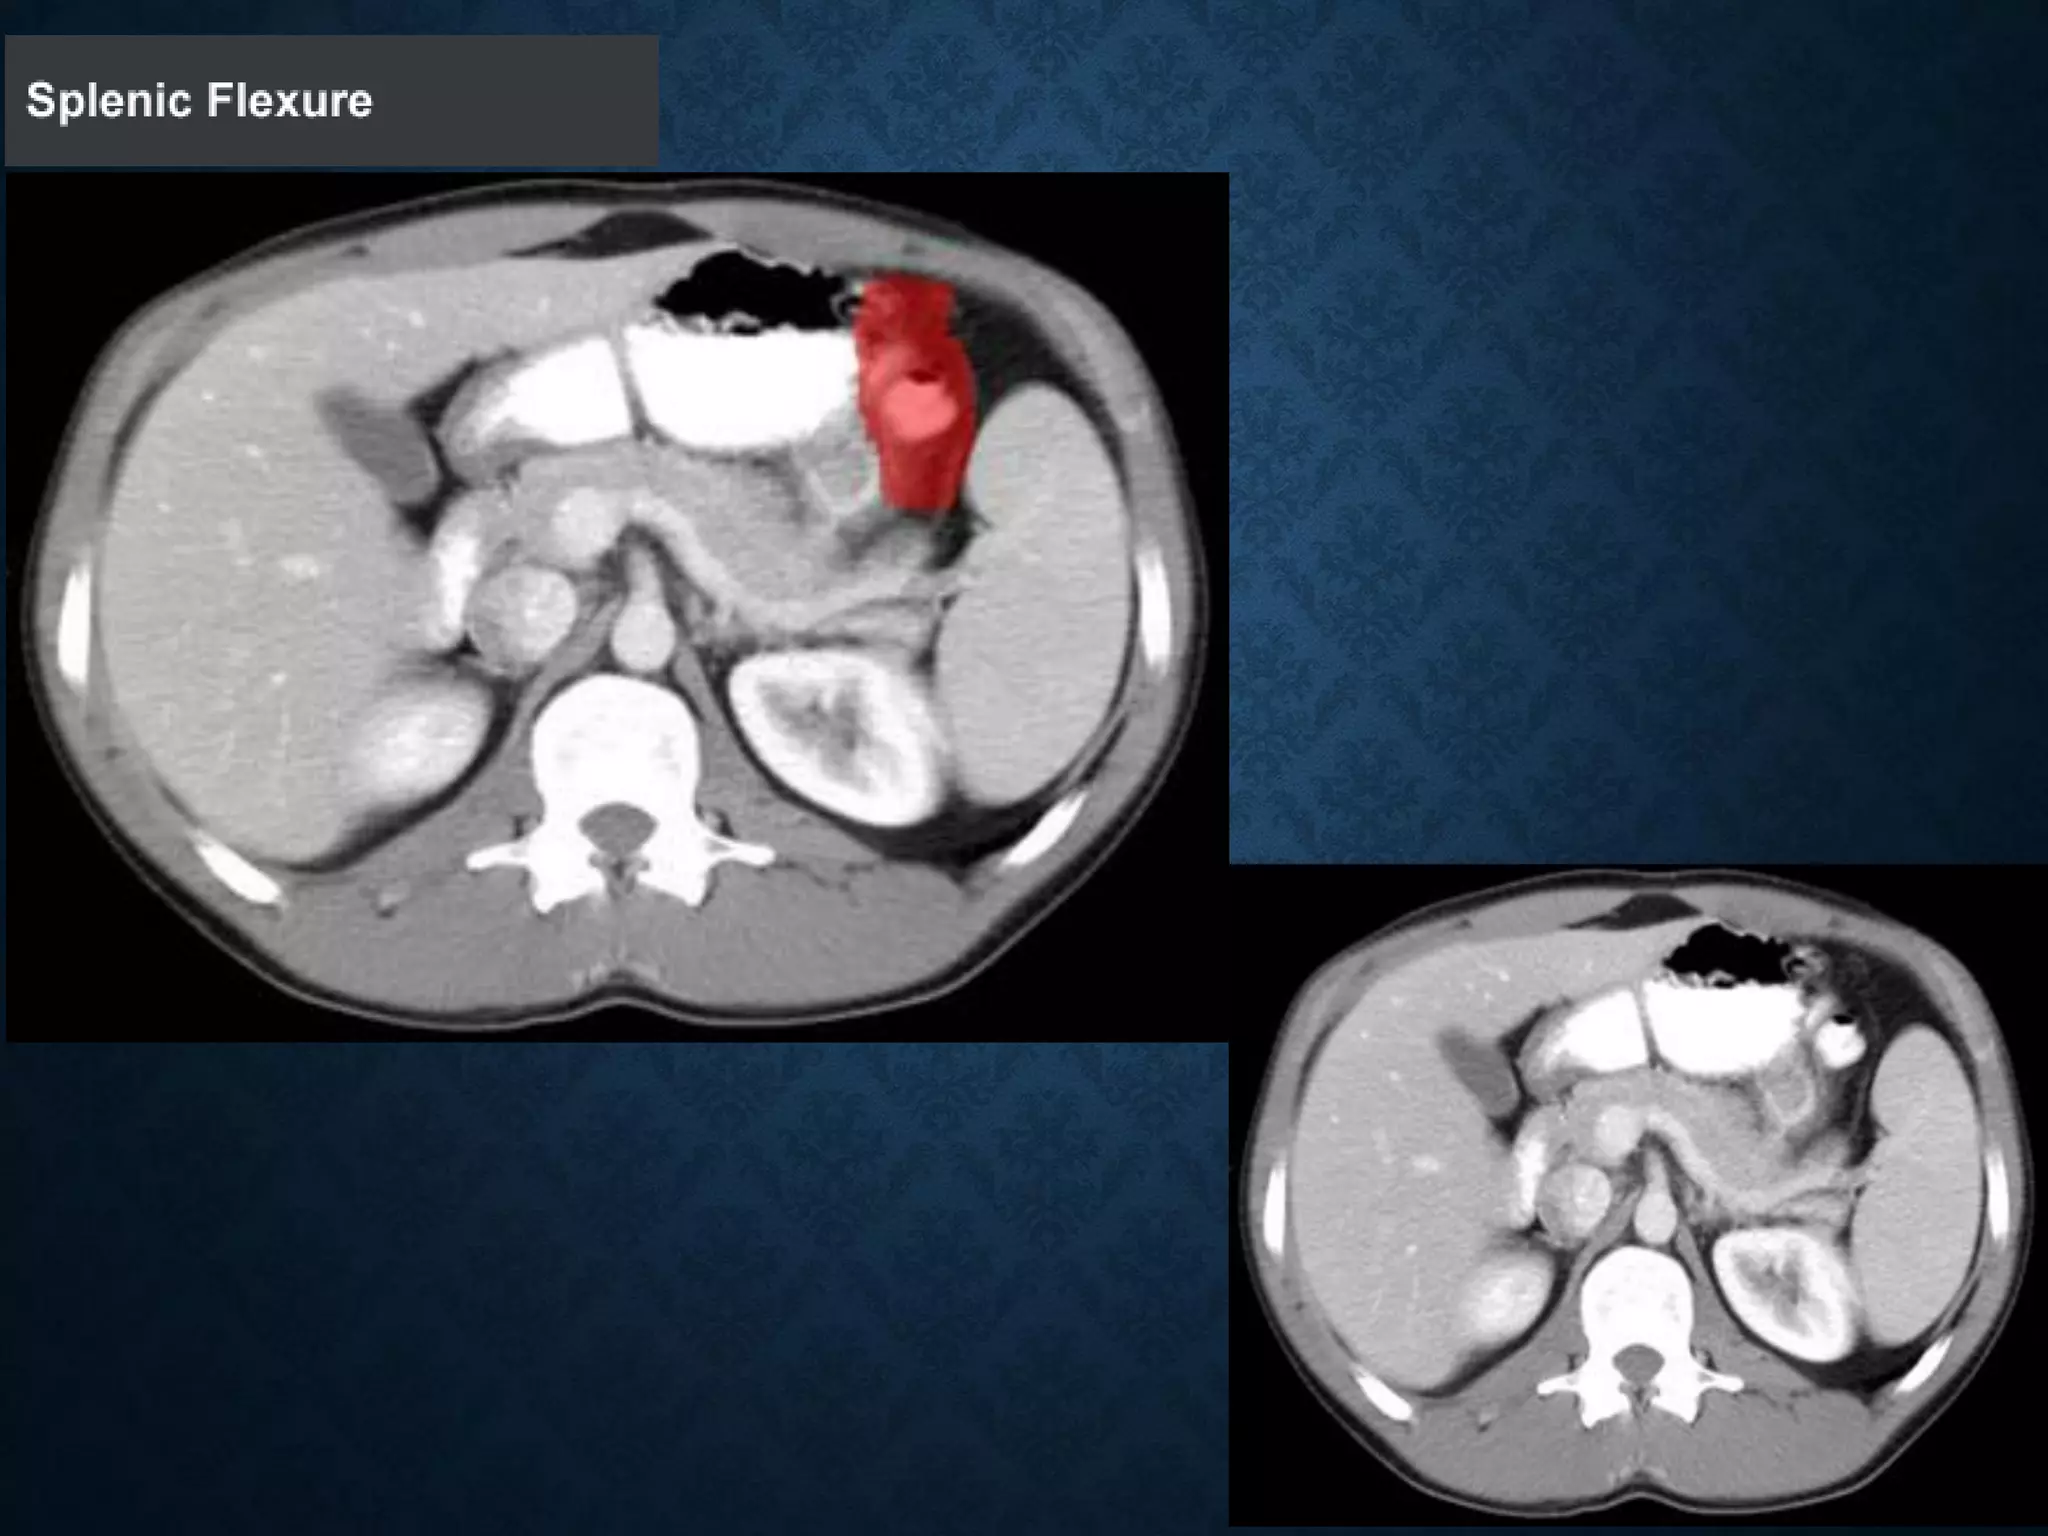

Identify the following structures in the body CT to the right. To view the location of the structure in the image click on

the label at the left and the structure will be indicated in the image. Abdominal CT scans typically begin just above

the diaphragm, so the first slice you see is of the lower chest.